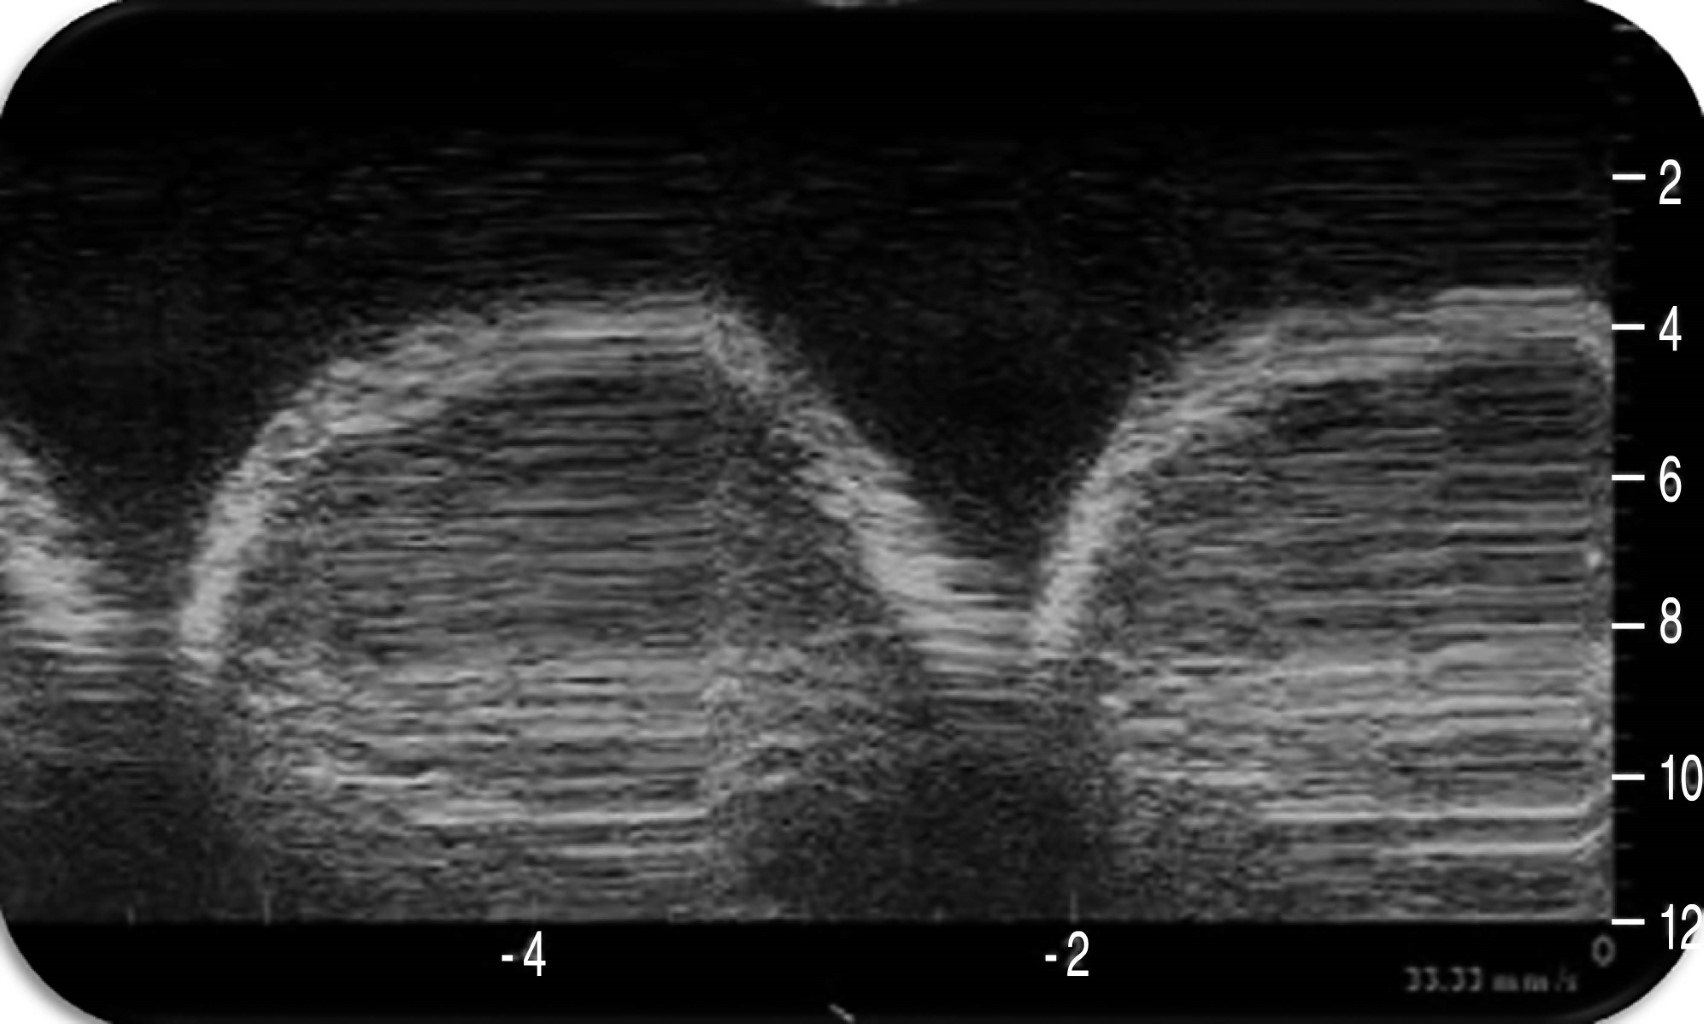

En modo M podemos ver la imagen en "arena de playa" constituida por un patrón lineal que corresponde a la pared torácica inmóvil, una línea hiperecogénica (la línea pleural) y un patrón granulado que correspondería al tejido pulmonar en movimiento. Este patrón granulado es más claro durante la inspiración permitiendo distinguir la fase respiratoria (Figura 2)(5).

Figura 2